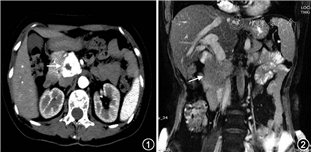

患者女,51岁。因“血压间断升高1个月余”入院。患者于1个月前在当地医院体检时测量血压170/110 mmHg(1 mmHg=0.133 kPa),休息数分钟后复测血压为140/90 mmHg。动态血压监测显示约28%日间时间收缩压大于140 mmHg,最高达156 mmHg(未见报告)。病程中偶有心慌不适,无头晕、头痛,无胸闷、乏力,无视野缺损,无恶心、呕吐等特殊症状。既往史:曾于当地医院诊断为“免疫性血小板减少”(未见报告),未予药物治疗。有间断头痛病史15年,未予特殊治疗。其父母有高血压病史。入院体检:体温36.5 ℃,脉搏65次/min,呼吸20次/min,血压106/79 mmHg。颜面部稍圆,四肢较纤细,未见水牛背及皮肤紫纹。腹软,腹部无压痛及反跳痛,肝、脾肋下未及,双下肢轻度指凹性水肿。实验室检查:血皮质醇水平升高且正常昼夜节律消失,小剂量(1 mg)午夜法及大剂量(8 mg)两日法地塞米松抑制试验均未被抑制(表1)。血电解质示持续性低钾血症,低钾时查24h尿电解质提示有肾脏尿钾排泄增加;动脉血气分析示代谢性碱中毒;肿瘤标记物检测示糖链抗原72-4(CA72-4)升高,甲胎蛋白(AFP)稍高于正常值;血浆肾素-醛固酮系统、儿茶酚胺及其代谢物检测(24h尿和血)未见异常;血常规提示血小板低;肝肾功能、空腹血糖正常;甲状腺功能示游离甲状腺素(FT4)、游离三碘甲状腺原氨酸(FT3)偏低,促甲状腺激素(TSH)以及甲状腺相关抗体未见异常(表2)。动态血压监测提示全天27%的时间收缩压大于140 mmHg,最高收缩压为148 mmHg,舒张压大于90 mmHg的比例为8%,最高舒张压96 mmHg,同时血压低于120/80 mmHg的时间占8%,白天血压平均值133/80 mmHg,夜间血压平均值133/76 mmHg,血压昼夜节律消失。12导联常规心电图正常。腹部彩色多普勒超声检查:胰头部实质性占位性病变(3.1 cm×3.2 cm);腹部增强CT:腹膜后见明显强化结节影,大小约36 mm×34 mm,边界尚清,与胰腺钩突、门静脉关系密切,门静脉受压(图1)。腹部磁共振-灌注成像:腹膜后肿瘤性病变(3.2 cm×2.7 cm),病灶弥散受限,动脉期明显强化,其内可见无强化期,延迟期强化程度未见明显减退,腹膜后肿瘤性病变(3.2 cm×2.7 cm),与胰腺钩突、门静脉关系密切(图2)。为进一步手术前评估肿瘤,行全身肿瘤代谢显像:(1)胰腺钩突区软组织肿块,代谢增高,考虑肿瘤性病变可能性大;(2)双侧肾上腺稍增粗,代谢轻度增高。综合以上诊断考虑:高血压原因待查,库欣综合征(ACTH依赖性)。